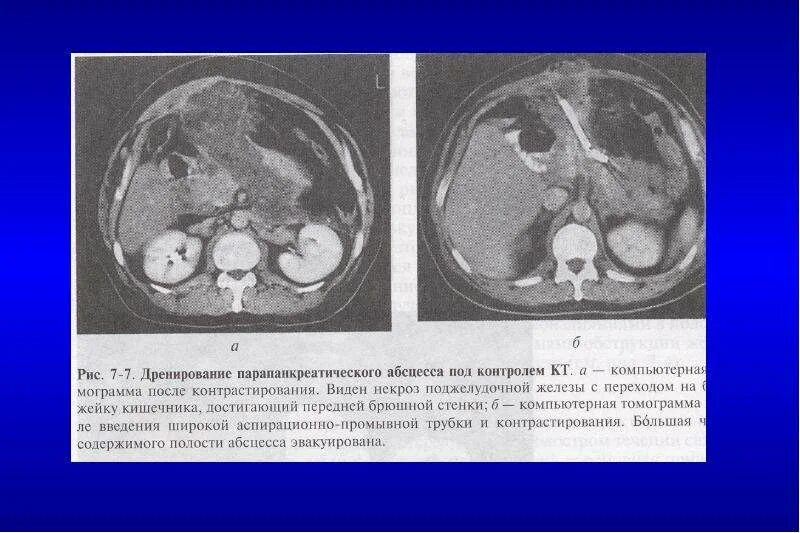

Инфильтрация паранефральной клетчатки на кт. параколитическая клетчатка кт. парапанкреатическая клетчатка инфильтрирована. перипанкреатический инфильтрат.Кт при остром панкреатите. парапанкреатическая клетчатка. кт диагностика панкреатита. острый отечный панкреатит кт.Парапанкреатическая клетчатка. поддиафрагмальное пространство. внебрюшинное поддиафрагмальное пространство. парапанкреатическая клетчатка инфильтрирована.Парапанкреатическая клетчатка что это значитКлетчатка анатомия. понятие о клетчатке в анатомии. основы клинической анатомии. клетчатка понятие.Парапанкреатическая клетчатка что это значитПарапанкреатическая клетчатка. парапанкреатическая клетчатка инфильтрирована. парапанкреатическая инфильтрация. парапанкреатическая клетчатка дифференцирована.Парапанкреатическая клетчатка что это значитПарапанкреатическая клетчатка что это значитХронический панкреатит на кт. парапанкреатическая клетчатка на кт. кт поджелудочной железы. поджелудочная железа на рентгенограмме.Парапанкреатическая клетчатка что это значитПарапанкреатическая клетчатка что это значитПарапанкреатический инфильтрат. парапанкреатическая клетчатка дифференцирована.Парапанкреатическая клетчатка что это значитПарапанкреатическая клетчатка что это значитПарапанкреатическая клетчатка поджелудочной железы. отек парапанкреатической клетчатки. парапанкреатическая инфильтрация. острый деструктивный панкреатит кт.Парапанкреатическая клетчатка что это значитПарапанкреатическая клетчатка что это значитПарапанкреатическая клетчатка что это значитПарапанкреатическая клетчатка что это значитПарапанкреатическая клетчатка что это значитПарапанкреатический инфильтрат. перипанкреатический инфильтрат. парапанкреатическая псевдокиста на кт.Парапанкреатическая клетчатка что это значитПарапанкреатическая клетчатка что это значитПарапанкреатическая клетчатка что это значитПарапанкреатическая клетчатка что это значитПарапанкреатическая клетчатка что это значитПарапанкреатическая клетчатка что это значитПарапанкреатическая клетчатка что это значитПарапанкреатическая клетчатка что это значитПарапанкреатическая клетчатка что это значитПарапанкреатическая клетчатка поджелудочной железы. перипанкреатический инфильтрат. осложнения острого панкреатита презентация. перипанкреатическая клетчатка.Парапанкреатическая клетчатка что это значитКисты и свищи поджелудочной железы. инфильтрация парапанкреатической клетчатки. истинные кисты поджелудочной железы классификация. парапанкреатическая клетчатка поджелудочной железы.Парапанкреатическая клетчатка что это значитПарапанкреатическая клетчатка что это значитПарапанкреатическая клетчатка что это значитПарапанкреатическая клетчатка что это значитПарапанкреатическая клетчатка что это значитПарапанкреатическая клетчатка что это значит